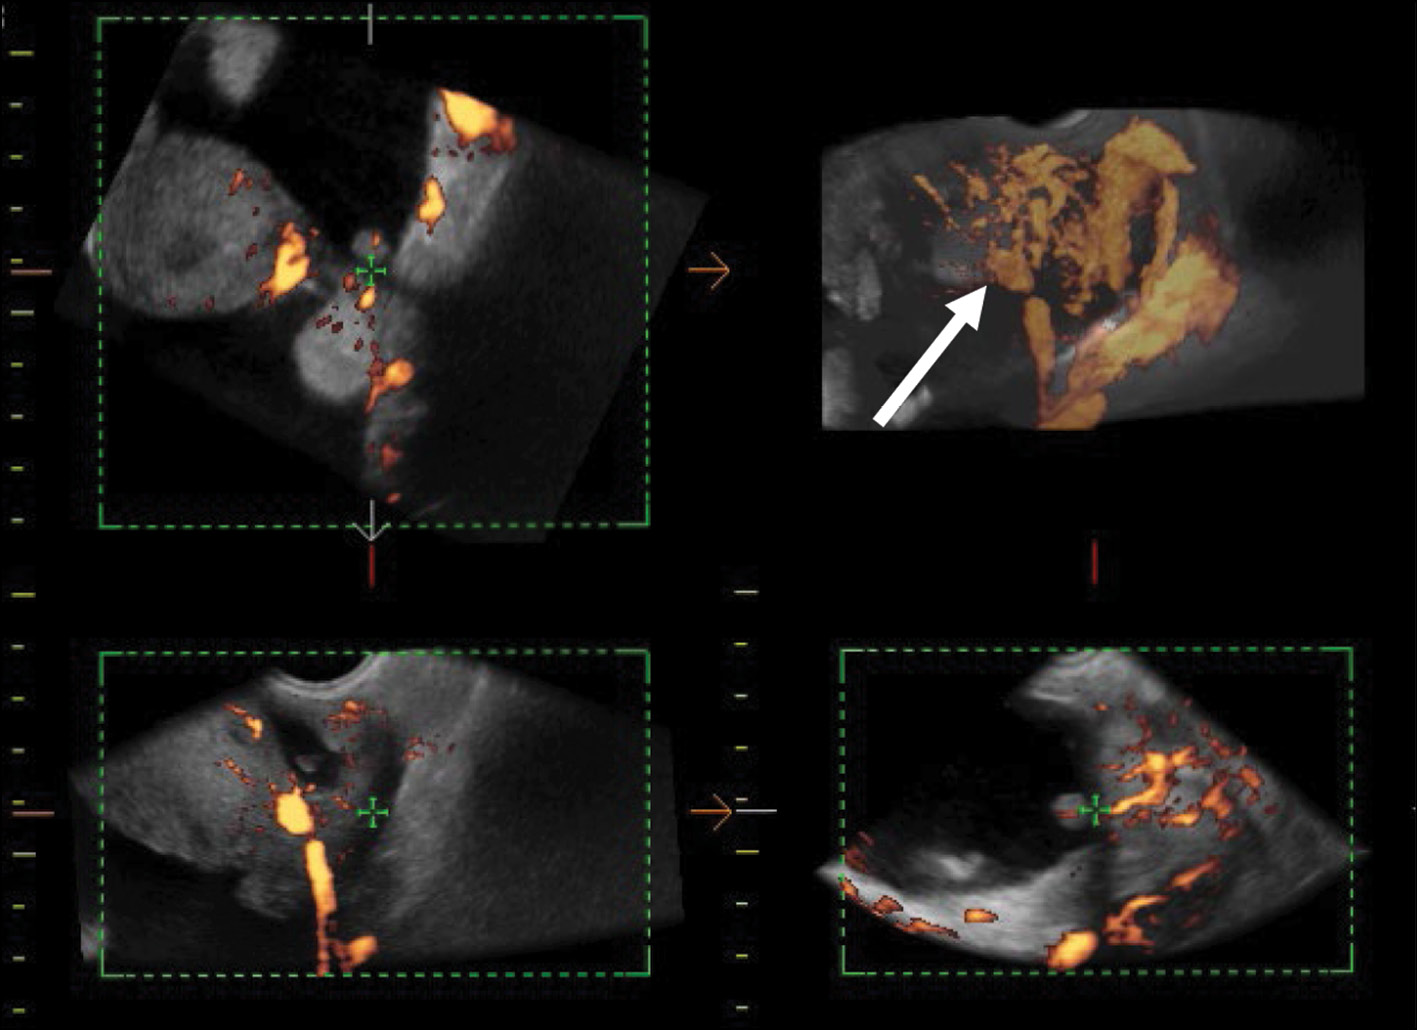

After diagnostic laparoscopy and biopsy of lesions in the pelvic peritoneum performed in another medical institution, complex ultrasonography was performed at the RRCR. An inhomogeneous isohypoechoic mass with areas of an anechoic structure of irregular and rounded shape was found in the projection of the right appendages. Pronounced pathological blood flow in the solid component of the mass, ascites, and carcinomatosis of the peritoneum of the small pelvis were also found. Figure 1 shows a 3D angiogram of the primary malignant struma ovarii on the right ovary.

Fig. 1. 3D angiography of a poorly differentiated malignant struma ovarii on the right (arrows).

eSaote Pro machine US was used; the transvaginal transducer and volume transvaginal transducer were used. Ultrasonography was performed in a standard 2D mode, and high-tech US methods were then used: power Doppler mapping, US computed tomography (CT), and 3D angiography.